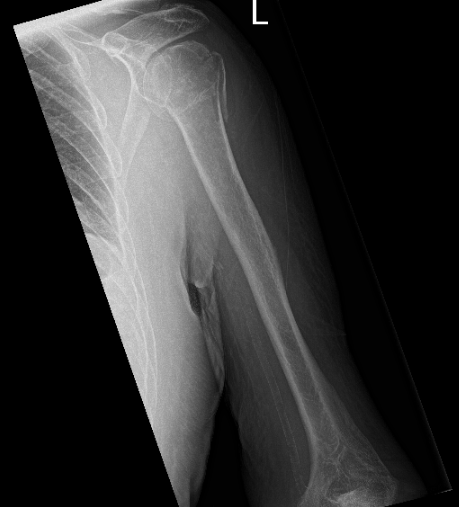

Patient seen today having complaints with his left shoulder. He stated that he fell off a ladder. And his left shoulder is the most affected one. He brings his X-ray with him. X-ray noted a comminuted fracture of the humeral head and neck and no change in position of fracture fragments compared to the left shoulder.

X-ray of the left shoulder